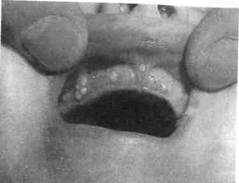

| Рис. 12.2. Папиллома слизистой оболочки красной каймы нижней губы. 44Г1 |

Опухоли чаще обнаруживают на слизистой оболочке нижней губы, альвеолярного отростка и языка,

Папиллома (рис. 12.2). Среди эпителиальных опухолей из многослойного плоского эпителия папилломы занимают второе место после сосудистых опухолей. Папилломы, как правило, встречаются в возрасте

7—12 лет, у девочек в 1,9 раза чаще. Эти опухоли локализуются на языке, губах, в области твердого и мягкого неба. Опухоль представляет собой разрастание сосочкового характера в виде выступа округлой или овальной формы, кустика (вид цветной капусты), чаще единичное, иногда множественное. Папилломы могут иметь блестящую гладкую поверхность и в этом случае их трудно дифференцировать от фибромы. Они бывают на широком основании или на ножке, имеют бледно-розовую окраску, соответствующую окраске окружающей слизистой оболочки. Длительно существующие папилломы вследствие ороговения поверхностного слоя эпителия приобретают белесоватую окраску, становятся более плотными, шероховатыми. При хронической травме папилломы бывают темно-красными, синюшно-красными с явлениями изъязвления. Растут медленно. Дифференцируют папиллому от фибромы, желез Серра.